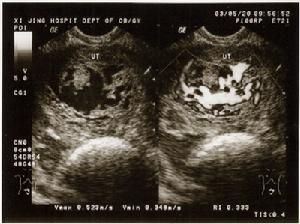

(3)卵巢黃素囊腫葡萄胎患者由於大量HCG的刺激,雙側或一側卵巢往往呈多發性囊腫改變。一般不產生症狀,偶有急性扭轉致急腹痛。葡萄胎清除後黃素囊腫可自行消退。黃素囊腫可貯藏大量HCG,故葡萄胎排出後合併有巨大黃素囊腫的患者,血和尿HCG消失比一般患者慢。

3.超聲檢查

正常妊娠在孕4~5周時,可顯示妊娠囊,孕6~7周可見心管搏動,最早在孕6周時即可探測到胎心,孕12周后均可聽到胎心。葡萄胎時宮腔內呈粗點狀或落雪狀圖像,無妊娠囊可見,亦無胎兒結構及胎心搏動征,只能聽到子宮血流雜音,聽不到胎心。